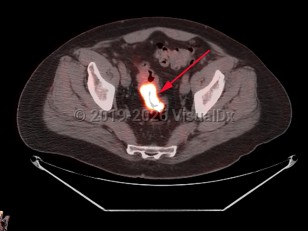

Rectal carcinomaRectal carcinoma

Bladder cancerBladder cancer

Fecal impaction